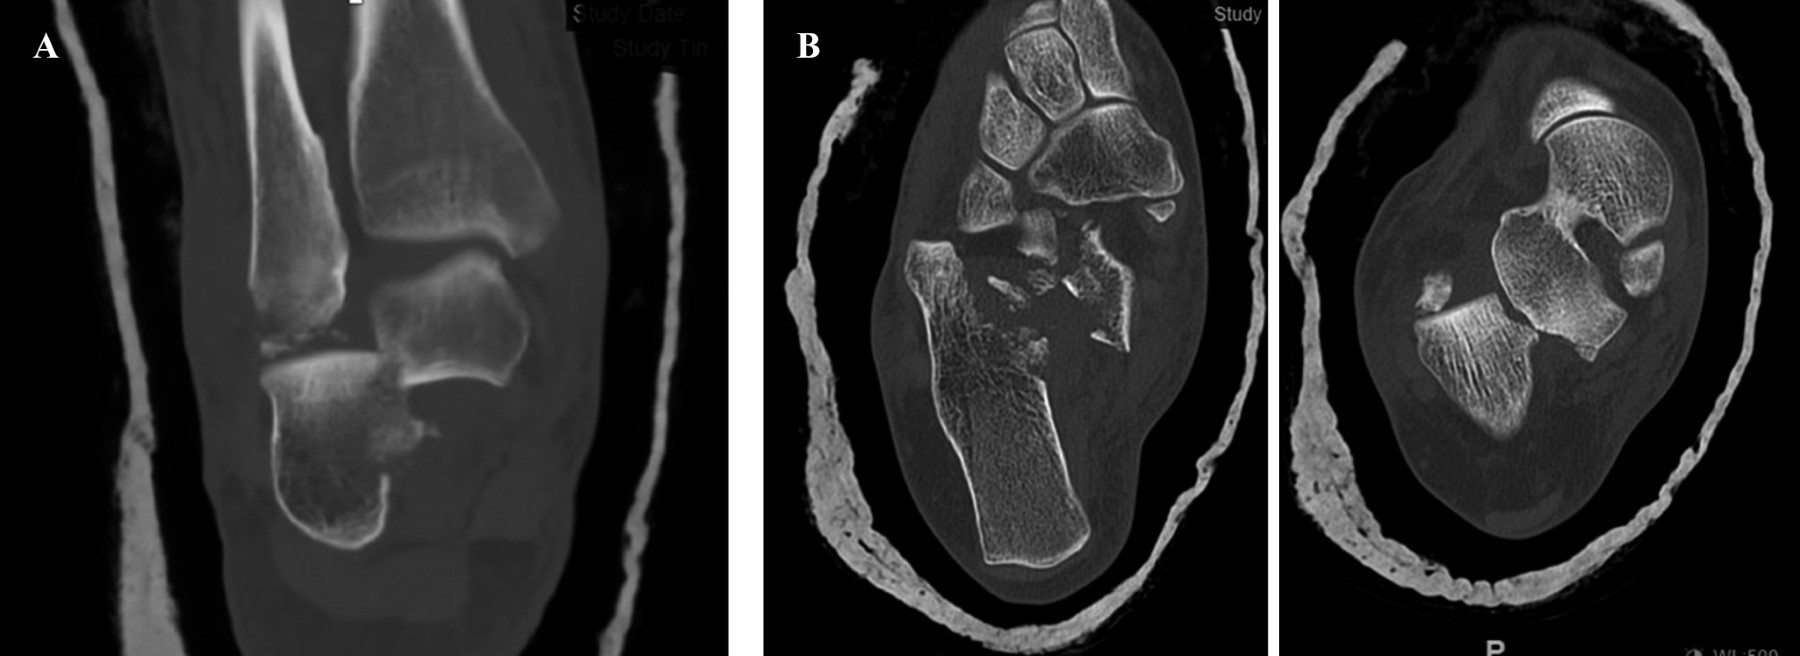

Introduction: subtalar dislocations, typical of high-energy trauma, are classified as medial, lateral, anterior or posterior depending on the deviation of the foot in relation to the talus. Lateral dislocation accounts for 17% of the total and has a worse prognosis. Immediate reduction is required to reduce the risk of sequelae, the incidence of which is around 90%. Objective: a case of lateral subtalar dislocation is presented; a review of the literature on its diagnosis, treatment and prognosis is carried out. Clinical case: a 46-year-old woman fell from a height of 3 meters, with severe deformity in the hindfoot. There was good distal vascular coloration, but no pulse or posterior tibial sensitivity could be identified. In addition, she had a medial sulcocutaneous fold under the head of the talus. Plain radiograph and CT revealed lateral subtalar dislocation, with fracture of the sustentaculum tali, and a "fleck sign" in the posterior region of the distal fibula. Suspecting soft tissue incarceration, a medial approach was performed, observing interposition of the posterior tibial neurovascular bundle. After joint reduction, the sustentaculum tali and the "fleck sign" were osteosynthesized. In addition, a complete section of the long lateral peroneal tendon was identified, which was tenodesed to the short peroneal tendon. Finally, an external fixator was placed. After eight weeks, the fixator was removed and weight bearing was authorized; after six months, mobility was complete and hypoesthesia persisted only in the plantar pad. Conclusions: lateral subtalar dislocation is an uncommon entity with a poor prognosis. Adequate interpretation through a thorough examination and pre-reduction CT of the bone and soft tissue lesions minimizes future sequelae.

Figure 2

Figure 3